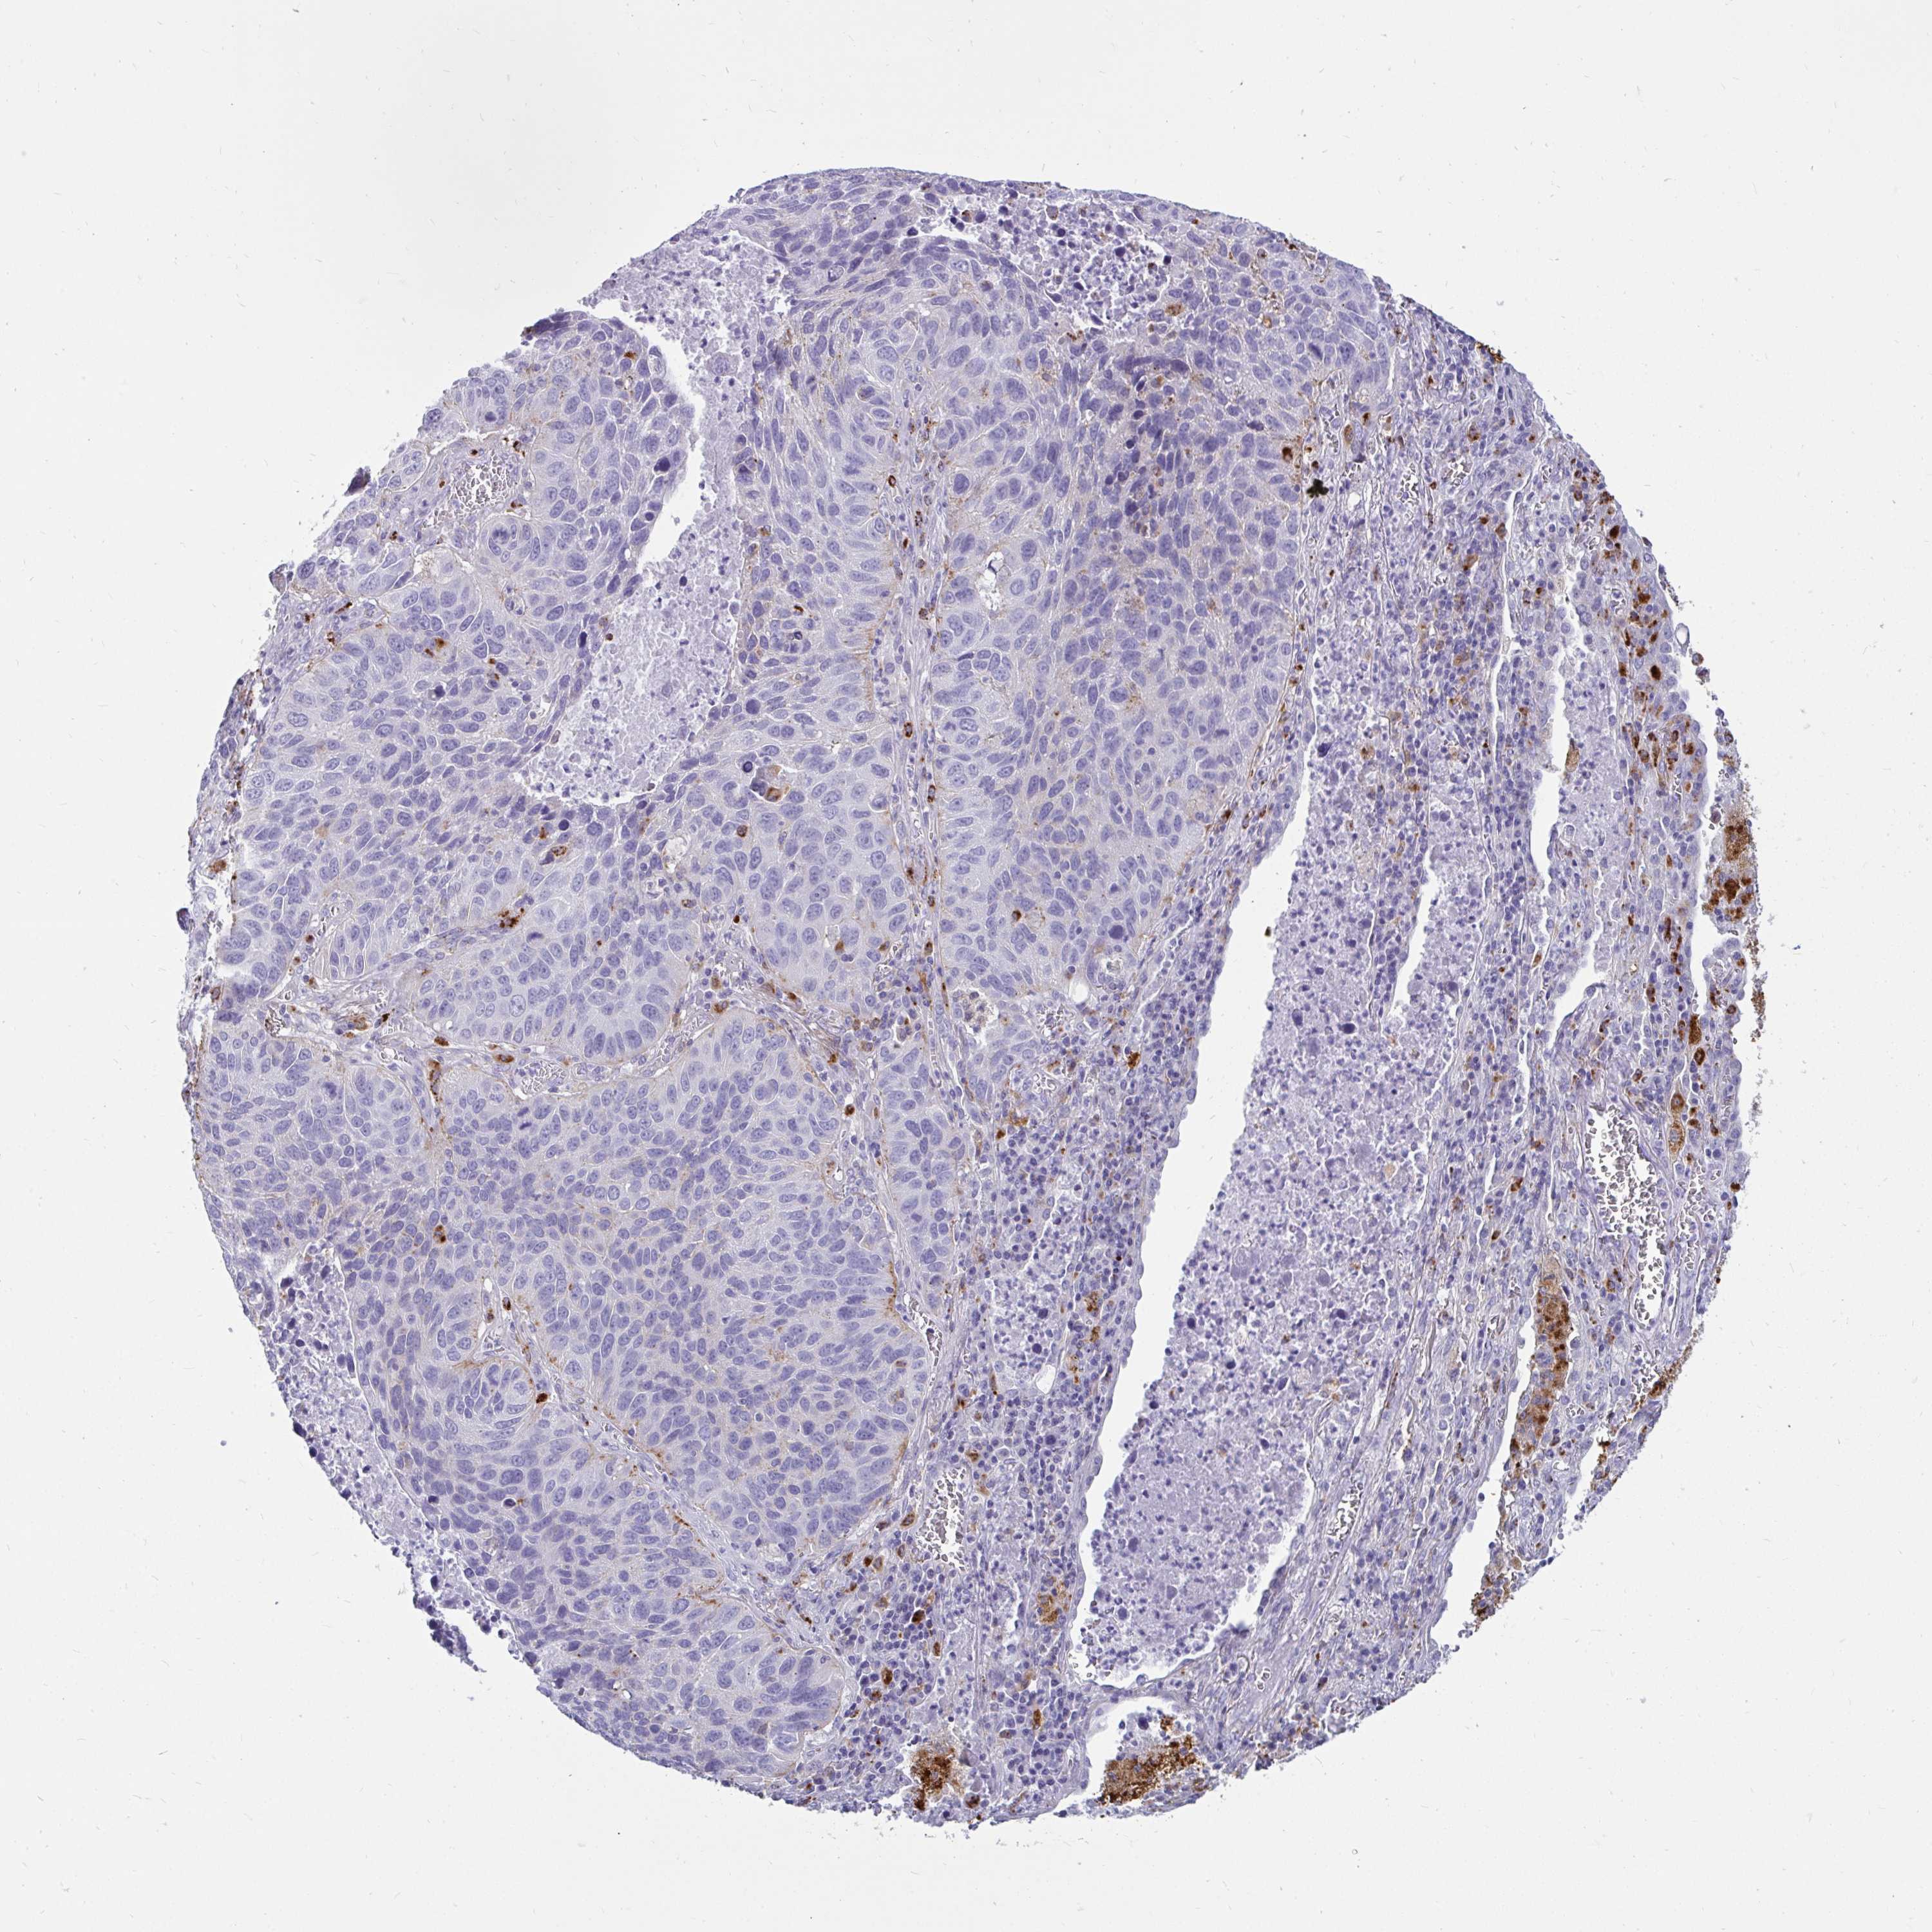

LUNG ADENOCARCINOMA (VALIDATION) - Interactive survival scatter ploti

The Survival Scatter plot shows the clinical status (i.e. dead or alive) for all individuals in the patient cohort, based on the same data that underlies the corresponding Kaplan-Meier plots. Patients that are alive at last time for follow-up are shown in blue and patients who have died during the study are shown in red.

The x-axis shows the expression levels (FPKM) of the investigated gene in the tumor tissue at the time of diagnosis. The y-axis shows the follow-up time after diagnosis (years). Both axes are complimented with kernel density curves demonstrating the data density over the axes. The top density plot shows the expression levels (FPKM) distribution among dead (red) and alive patients (blue). The right density plot shows the data density of the survived years of dead patients with high and low expression levels respectively, stratified using the cutoff indicated by the vertical dashed line through the Survival Scatter plot. This cutoff is automatically defined based on the FPKM cutoff that minimizes the p-score. The cutoff can be changed by dragging the vertical line or by entering a cutoff value in the square labeled "Current cut-off".

Under the Survival Scatter plot the p-score landscape (black curve; left axis) is shown together with dead median separation (red curve; right axis). Dead median separation is the difference in median mRNA expression between patients who have died with high and low expression, respectively. It is calculated as follows: median FPKM expression of dead patients with high expression - median FPKM expression of dead patients with low expression. This is intended to aid the user in visually exploring custom cutoffs and the associated p-scores and dead median separation.

Individual patient data is displayed and can be filtered by clicking on one or more of the category buttons on the top of the page. Categories describing expression level and patient information include: high, low, alive, dead, female, male and tumor stages. The scale of the x-axis can be toggled between linear and log-scale by clicking on the "x log" button. Mouse-over function shows TCGA ID, patient information and mRNA expression (FPKM) for each patient.

& Survival analysisi

Kaplan-Meier plots summarize results from analysis of correlation between mRNA expression level and patient survival. Patients were divided based on level of expression into one of the two groups "low" (under cut off) or "high" (over cut off). X-axis shows time for survival (years) and y-axis shows the probability of survival, where 1.0 corresponds to 100 percent.

CTSZ is not prognostic in Lung Adenocarcinoma (validation)

: 272.58

Average pTPM 215.1

Number of samples 105